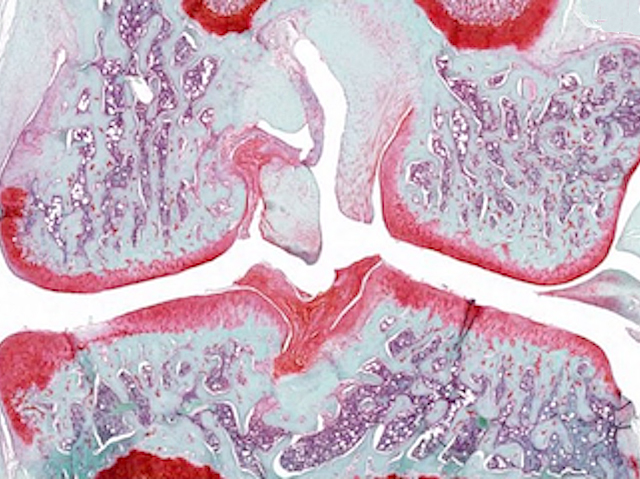

Les característiques que definixen les cèl·lules mare són la seua capacitat de convertir-se en diversos tipus cel·lulars i la seua habilitat per a autorenovar-se. Aquesta capacitat d’autorenovació garantix el manteniment de les reserves de cèl·lules mare en el cos i, si els científics saben aprofitar-la bé, també al laboratori. Quan es mantenen cultius de cèl·lules mare al laboratori, els investigadors solen utilitzar diferents combinacions de factors específics per a cada tipus de cèl·lula mare. No obstant això, investigacions recents han identificat un punt de control comú (la quinasa reguladora GSK3), que, quan s’inhibix, manté la capacitat d’autorenovació en diversos tipus de cèl·lules mare i en diferents espècies. De fet, la inhibició de GSK3 ha permés cultivar conjuntament epiblasts de ratolí i cèl·lules mare embrionàries, com es mostra a la imatge (en verd i roig), mantenint alhora les seues identitats pròpies, cosa que fins ara era impossible. A més de millorar les tècniques de cultiu de cèl·lules mare, el descobriment d’aquest punt de control comú podria tindre aplicacions clíniques per a millorar la salut i la regeneració de teixits envellits.

Imatge de Duo Wang/Ying Lab/USC Stem Cell. Publicació de Duo Wang i Xiukun Wang, i col·laboradors/es

Eli and Edythe Broad Center for Regenerative Medicine and Stem Cell Research at USC, Keck School of Medicine, USC, Los Angeles, CA; Epigenetics and RNA Biology Laboratory, National Institute of Environmental Health Sciences, Durham, NC, EUA

Publicat en Cell Research, abril de 2026